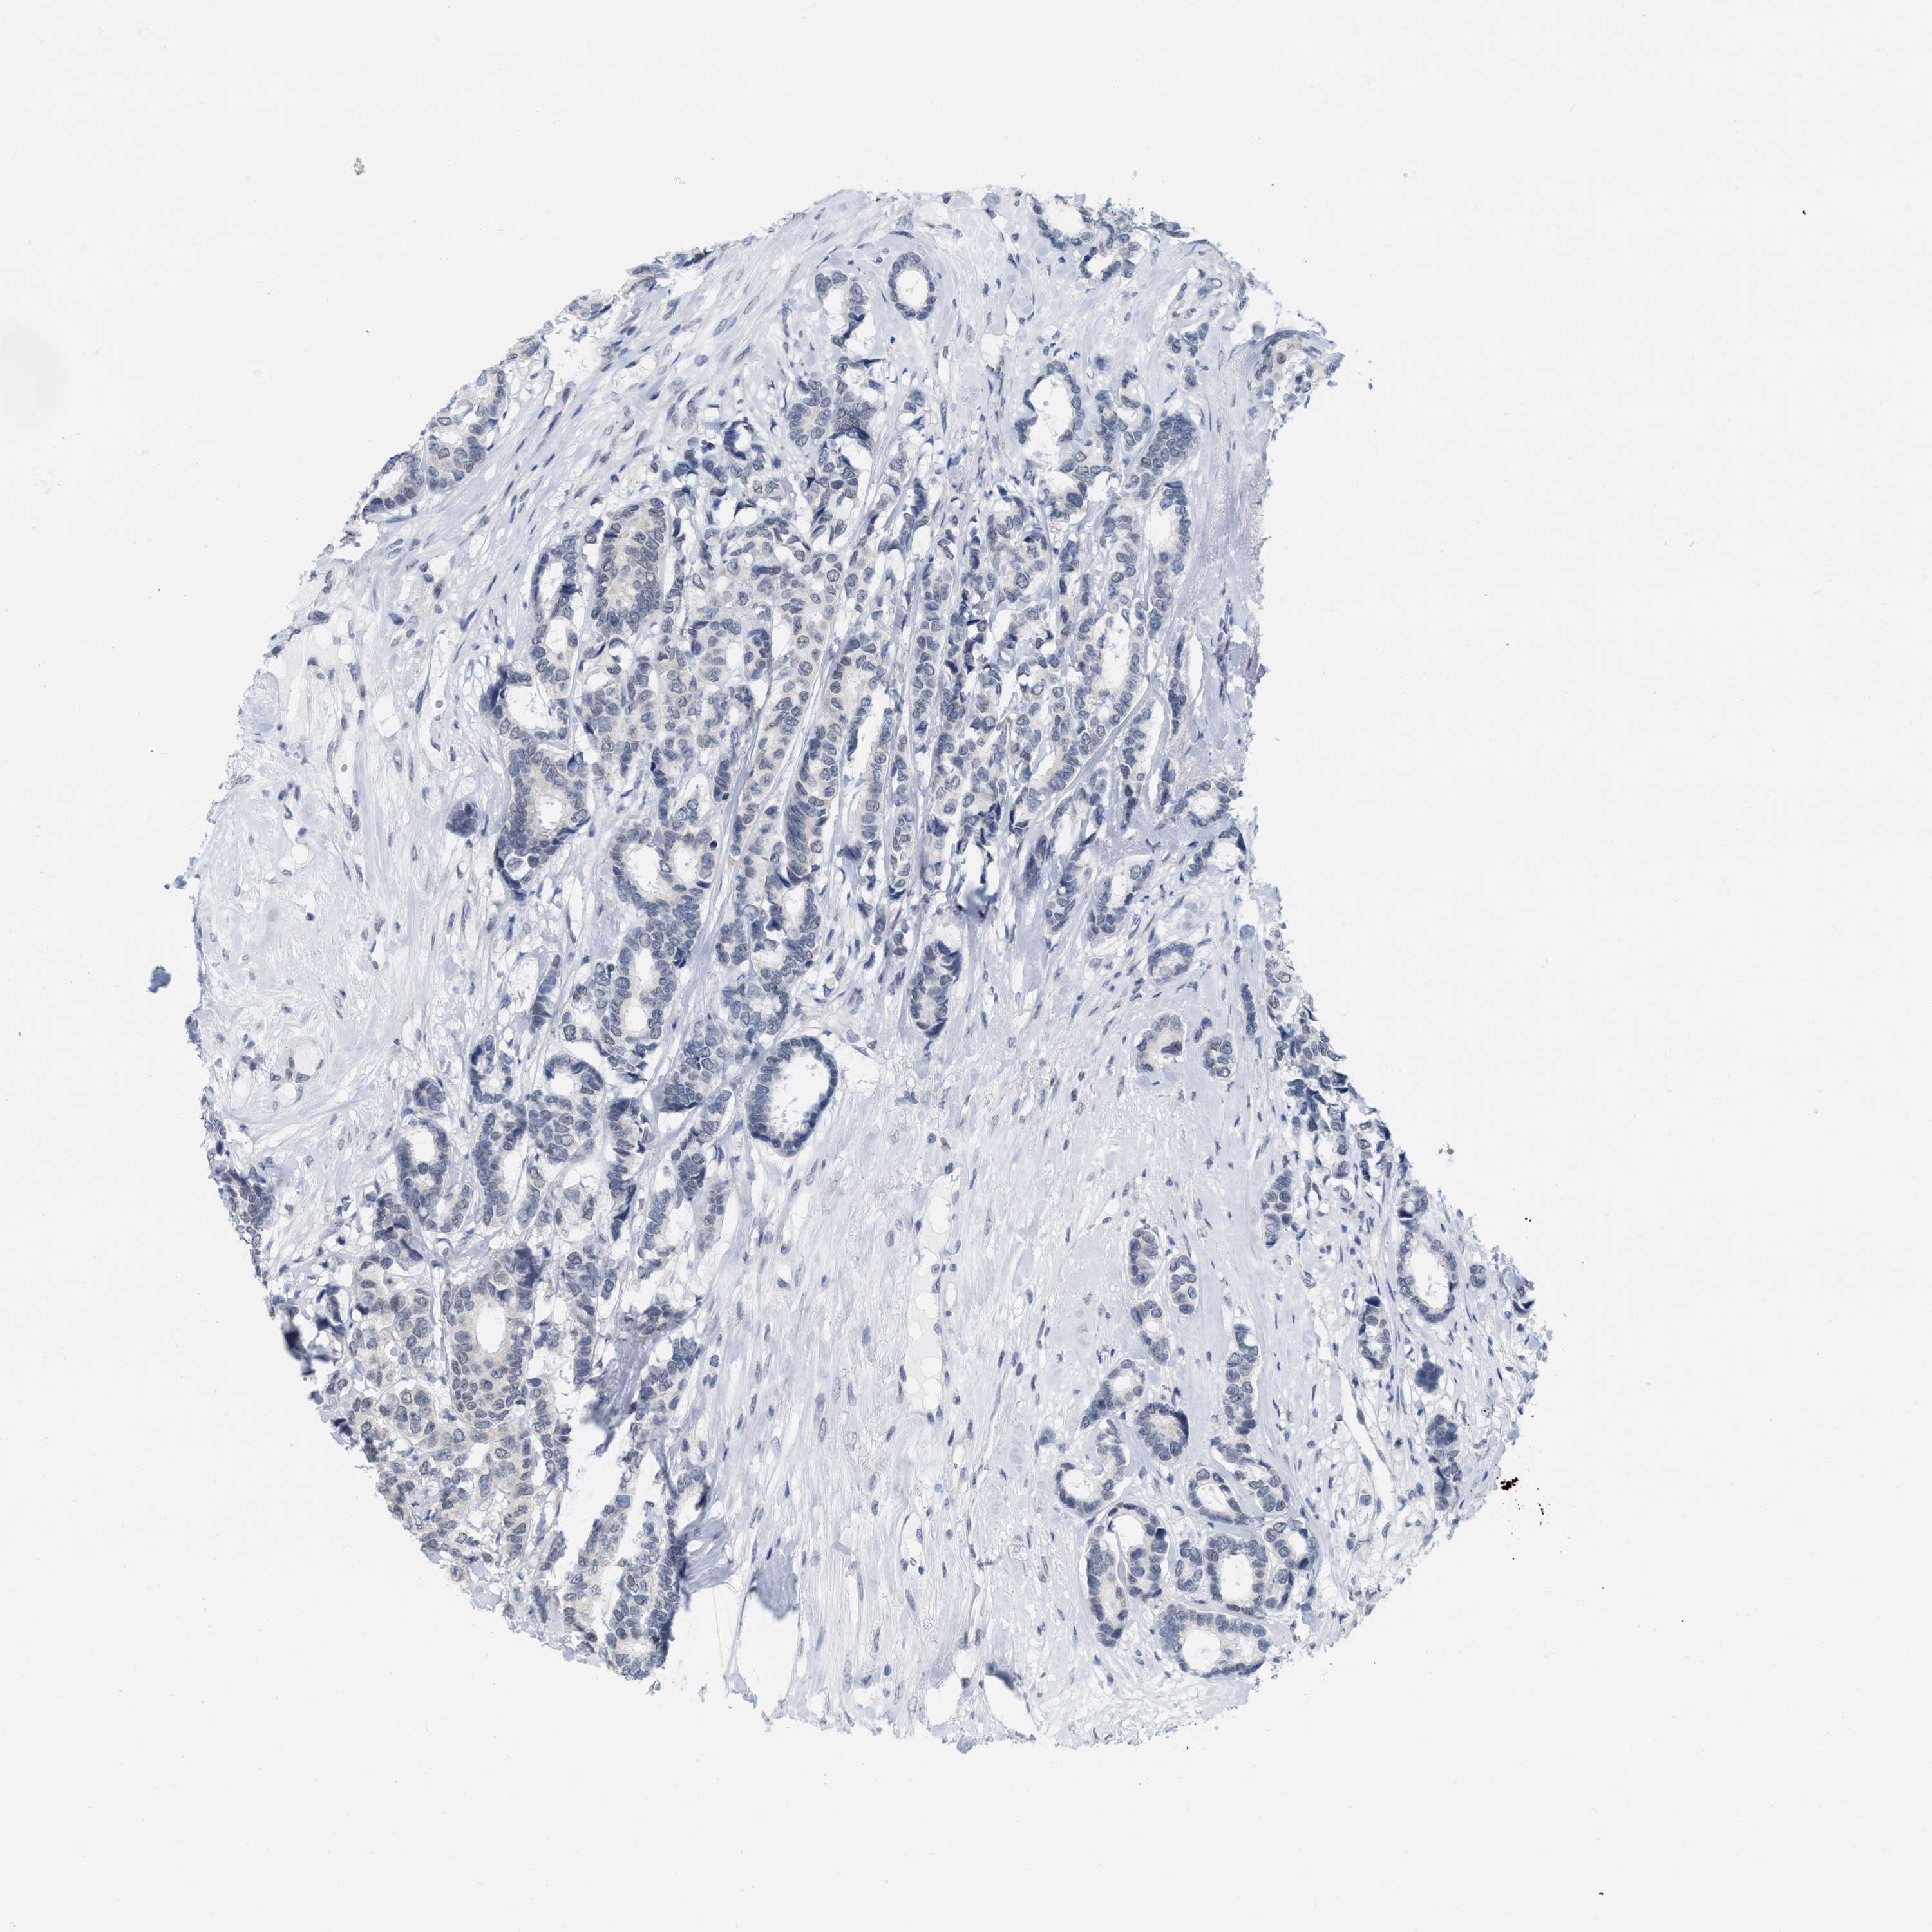

BRCA TCGA BRCA VALIDATION PROTEIN EXPRESSION

Breast cancer

Human cancer